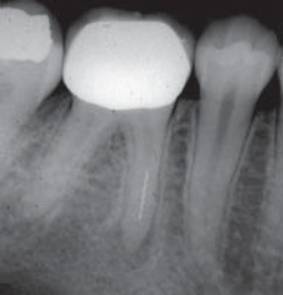

Снимок определения рабочей длины. Виден ByPass сломанного

инструмента.

Снимок наблюдения через 6

месяцев. Практически полное исчезновение периапикальных процессов на М и Д

корнях